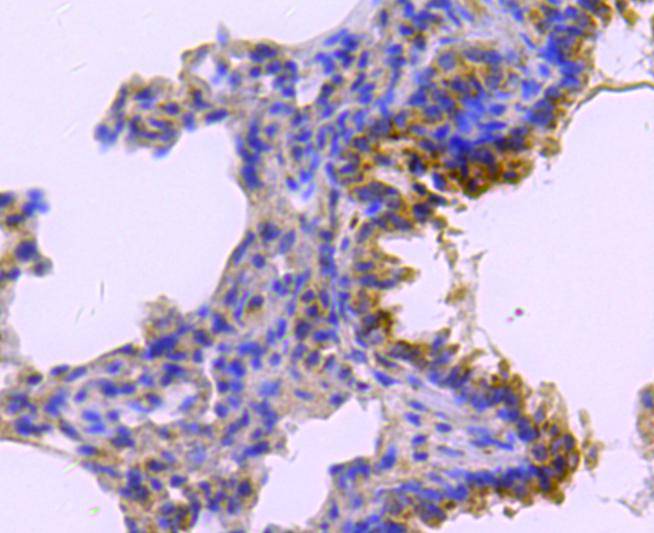

Immunohistochemical analysis of paraffin-embedded rat lung tissue using anti-catalase antibody. Counter stained with hematoxylin.